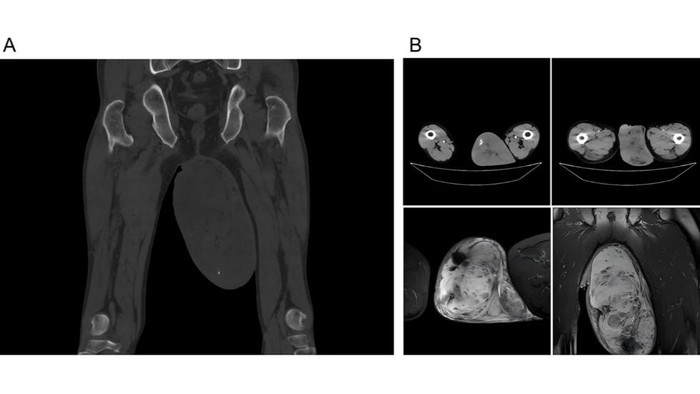

Kondisinya testis kiri pasien membengkak drastis, berukuran sekitar 123 x 168 mm atau sekitar 12,3 x 16,8 cm. Ukuran itu 3-4 kali lebih besar dari ukuran normal.

Di dalamnya, dokter menemukan massa yang jelas, keras, dan halus berukuran 12 x 15 cm.

Pasien menjalani operasi pengangkatan massa tersebut, dan akhirnya didiagnosis mengidap angiomyofibroblastoma atau AMF. Itu merupakan tumor jinak langka yang paling sering ditemukan di saluran genital bawah wanita pre-menopause, biasanya di area vulva.